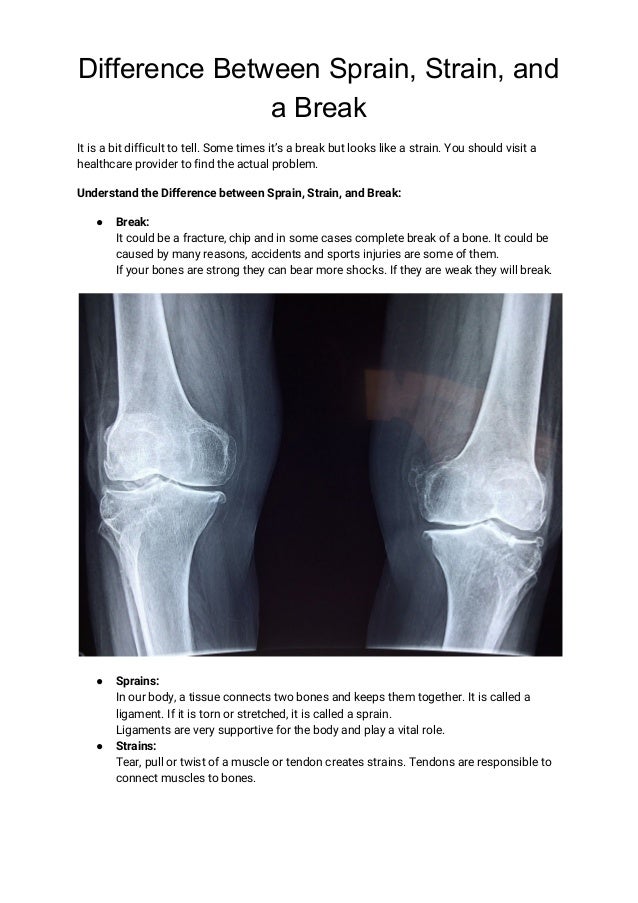

Difference between sprain, strain, and a break